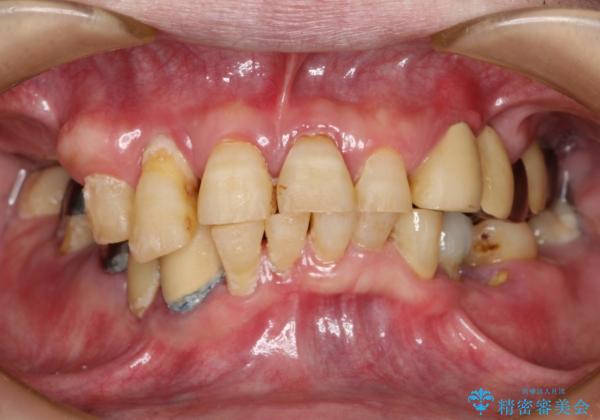

虫歯だらけ、歯周病 崩壊した口腔の再建 フルマウスリコンストラクション

- 歯周外科・インプラント・顕微鏡下根管治療などを含んだ総合的な治療を計画した。

様々な治療手段を高いレベルで同時に併行して行うことが必要でした。

かみ合わせの力が非常に強く、夜間の歯ぎしり・食いしばりもひどかったため、奥歯はメタルオクルーザルの設計でかぶせ物を製作しています。